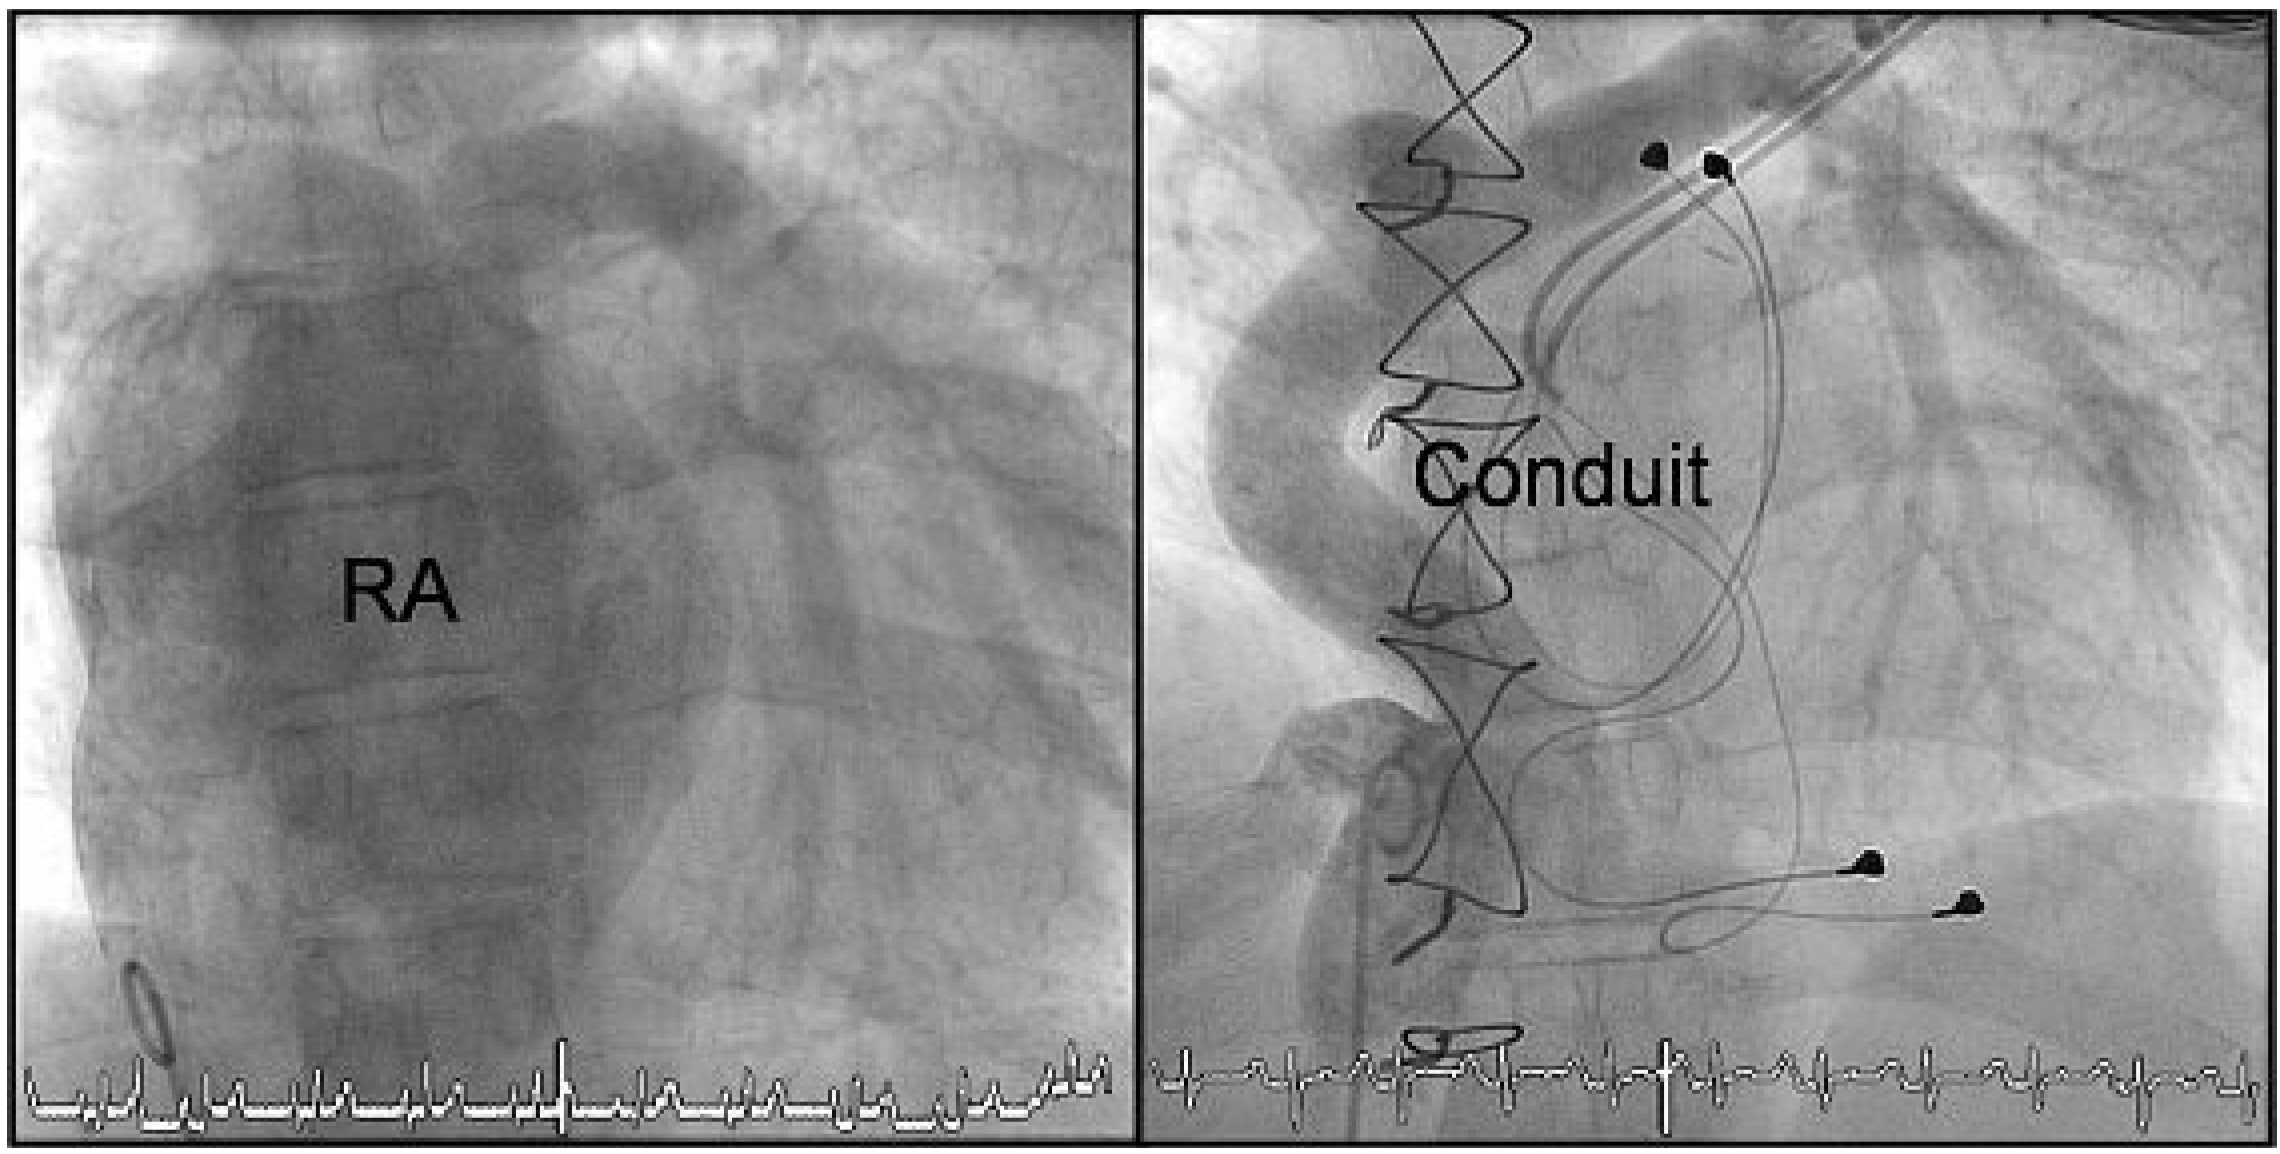

Abbildung 5.

Angiographie vor (links) und nach Fontan-Revision (rechts). Vor der Revisionsoperation wird das Blut von der Vena cava inferior und den Lebervenen über den riesigen RA in die pulmonale Zirkulation geleitet. Nach der Fontan-Revision zeigt sich der Konfluens der Vena cava inferior mit den Lebervenen in den extrakardialen Goretex-Conduit sowie dessen Anastomose zum Truncus pulmonalis unmittelbar proximal der Bifurkation. Durch die separate Mündung der Vena cava superior in die rechte Pulmonalarterie zeigt sich hier weniger Kontrastmittel (konkurrenzierender Fluss). Die epikardialen linksatrialen und linksventrikulären Elektroden des Schrittmachers sind ebenfalls erkennbar.

Abbildung 5.

Angiographie vor (links) und nach Fontan-Revision (rechts). Vor der Revisionsoperation wird das Blut von der Vena cava inferior und den Lebervenen über den riesigen RA in die pulmonale Zirkulation geleitet. Nach der Fontan-Revision zeigt sich der Konfluens der Vena cava inferior mit den Lebervenen in den extrakardialen Goretex-Conduit sowie dessen Anastomose zum Truncus pulmonalis unmittelbar proximal der Bifurkation. Durch die separate Mündung der Vena cava superior in die rechte Pulmonalarterie zeigt sich hier weniger Kontrastmittel (konkurrenzierender Fluss). Die epikardialen linksatrialen und linksventrikulären Elektroden des Schrittmachers sind ebenfalls erkennbar.

Eine Rechtsherzkatheteruntersuchung aufgrund prolongierter Diarrhoe eine Woche postoperativ zeigte eine gute funktionierende «neue» extrakardiale Fontan-Zirkulation (Abb. 5). In der Schrittmacherabfrage ergaben sich im weiteren Verlauf keine Hinweise für weitere Tachyarrhythmien. Bereits in der vierten postoperativen Woche leistete unsere Patientin in der Eintrittsuntersuchung für die ambulante kardiale Rehabilitation 10 METs (100% des Solls). Cordarone konnte in der Zwischenzeit abgesetzt werden. Die weiteren Schrittmacherkontrollen zeigten, dass der Grundrhythmus nun ein Sinusrhythmus war, die Patientin aber während der Ruhephasen atrial gepaced wurde (AAIR 70–145/min).